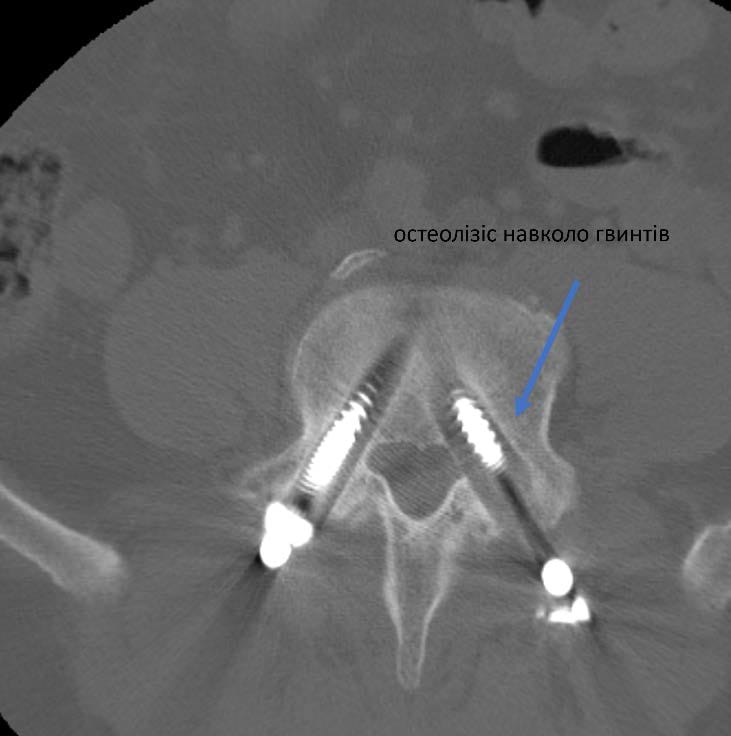

Усі повторні операції пов’язані з більшим ризиком ускладнень та потребують ретельного планування. «З одного боку це був цікавий випадок. З іншого – ми завжди допомагаємо нашим військовим з особливим задоволенням», - розповідає Олексій Леонтьєв. Склалося так, що у пацієнта було встановлено 6 гвинтів, з яких 1 поламався, 3 розхиталося і таким чином його хребет втратив опороздатність. Складність операції полягала і ще у тому, що зламану частину гвинта видалити практично неможливо і ставало питання про встановлення додаткових гвинтів та видалення тих що розхиталися. План був складений. На допомогу прийшли наші колеги (https://www.facebook.com/Implants.in.ua), які надали металоконструкцію, що була необхідна для пацієнта.

Це була складна операція. Вона тривала 7 годин. Розхитані та поломані гвинти було видалено, а також конструкцію було додатково укріплено ще гвинтами. Перепроведено тазовий гвинт. Також була виконана декомпресія корінця S1 що давав виражений больовий синдром.

Результати реоперації на наступних малюнках: